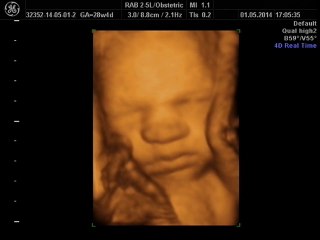

BCF Ultrason Görüntüsü - Hasvet Medikal

Uploaded: 2014-02-04